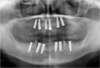

Programmation et mise en place des implants (6 implants maxillaires :haut et 6 mandibulaires : bas)

Radiographie implants en place